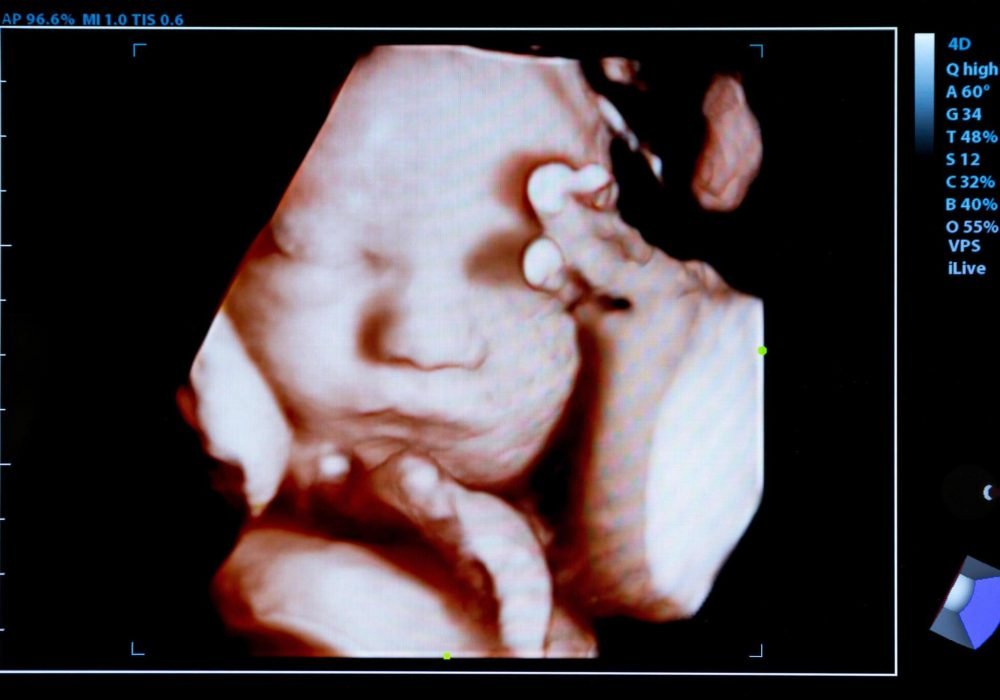

3D/4D Imaging:

Providing expectant parents with memorable and detailed images of their unborn child through advanced 3D/4D ultrasound technology. This service offers a unique bonding experience by allowing parents to see their baby’s features and movements in real-time.